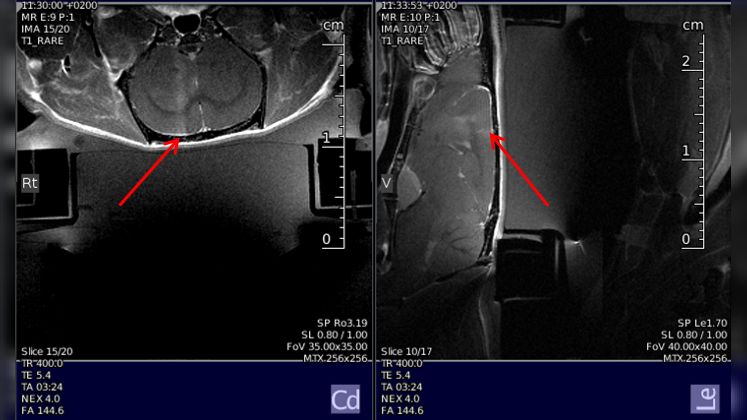

Read more →FUS with preclinical MRI allows brain drug delivery via BBB opening, localized heating, and MRI thermal mapping

Read more →MR measurements of nonliving samples, MR measurements in vivo (mice, rats)